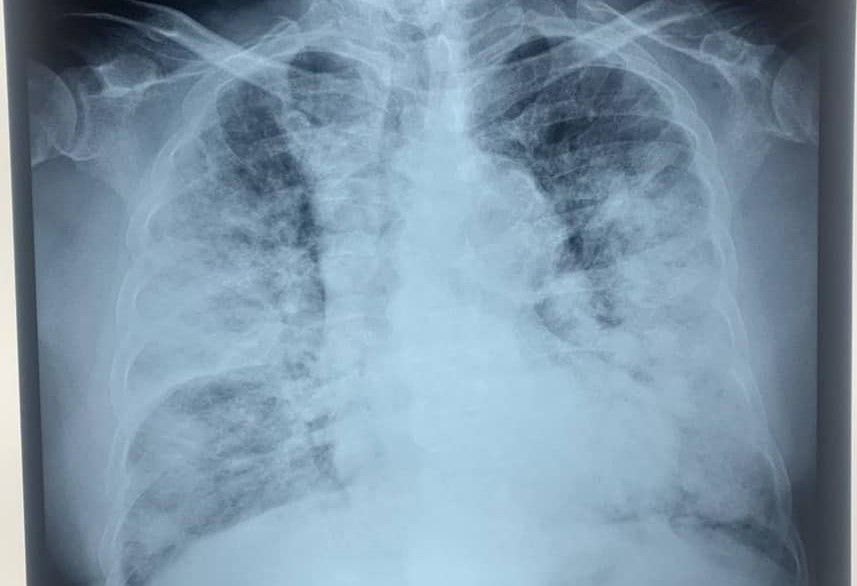

អ្វីគួរឲ្យកត់សម្គាល់ នៅលេខរៀងទី៥ ជាបុរសជនជាតិខ្មែរ អាយុ ២៤ឆ្នាំ រស់នៅក្រុងបាវិត ខេត្តស្វាយរៀង បានស្លាប់មុនពេលចូលដល់មណ្ឌលព្យាបាលជំងឺកូវីដ ១៩។ តាមរបាយការណ៍របស់មន្ទីរសុខាភិបាលខេត្តស្វាយរៀង បុរសខាងលើមានអាការៈក្តៅខ្លួន ក្អក ហត់ដង្ហក់ខ្លាំង បានចូលមកដល់មណ្ឌលព្យាបាលកូវីដ ១៩ បាវិត ពេលដល់មណ្ឌលព្យាបាលត្រូវបានគ្រូពេទ្យបញ្ជាក់ថា អ្នកជំងឺបាត់បង់ជីវិតទៅហើយមុនពេលមកដល់មណ្ឌលព្យាបាល នៅថ្ងៃទី២២ ខែមេសា ២០២១ វេលាម៉ោង៨៖០០។ ជាករណីសង្ស័យ សពត្រូវបានយកសំណាក ដោយទទួលបានលទ្ធផលវិជ្ជមានកូវីដ ១៩។